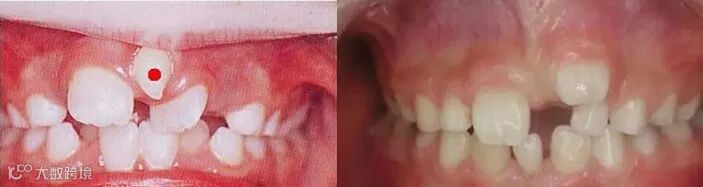

乳牙早失戴间隙保持器

门牙间隙过大(左侧图片为多生牙导致)